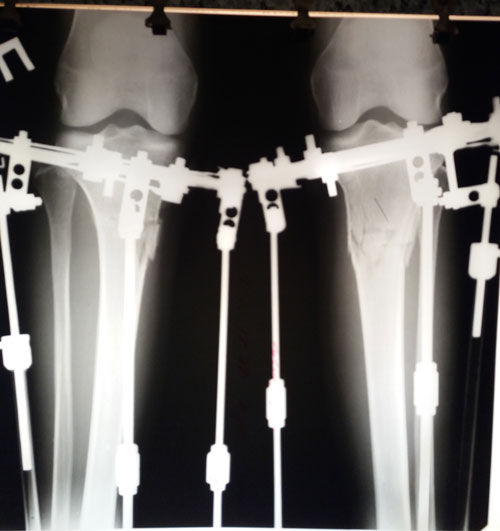

на фиксации.

рентген перед фиксацией.